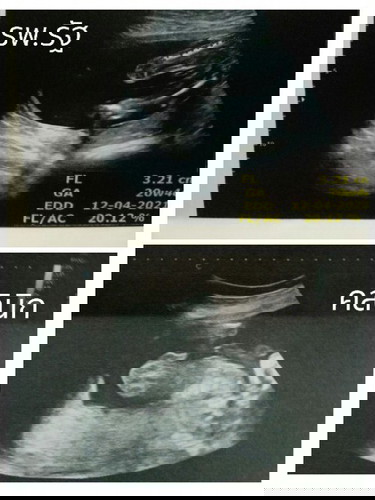

อัลตร้าซาวด์สัปดาห์ที่20 ครั้งแรกที่ รพ.รัฐ หมอแจ้งว่าน้องหนีบขาไว้ทำให้สังเกตเพศยาก และเดาว่าน่าจะเป็นเพศหญิง เพราะส่องไม่เห็นปิกกาจูน้อง อีกวันเลยไปซาวด์ที่คลินิก คุณหมอสังเกตเห็นเป็นเพศชาย แต่แม่ยังสังเกตไม่ออกเลยค่ะว่าดูยังไงแบบไหน ญ หรือ ช #ขอบคุณล่วงหน้านะคะ #ท้องแรกคะ